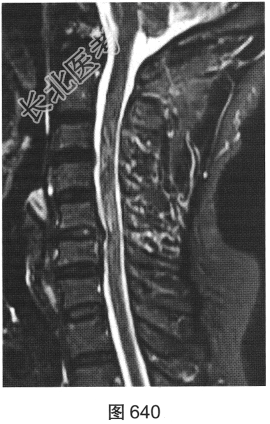

- [材料题] 患者女性,49岁,颈部胀痛伴双手麻木3天。MRI检查见图632~图637。

- 多项选择题1.患者MRI图片有哪些阳性征象( )

A、同水平硬膜囊及脊髓明显受压

B、病变与硬膜夹角为钝角

C、病变呈环形强化,中心未见明显强化

D、病变在髓外硬膜下

E、病变跨越右侧椎间孔,呈哑铃状改变

F、C

水平硬膜外梭形软组织信号

- 多项选择题2.根据MRI表现,患者可能的诊断是( )

A、脊柱淋巴瘤

B、椎间盘脱出、髓核游离

C、神经纤维瘤

D、后纵韧带骨化

E、神经鞘瘤

F、硬膜外血肿